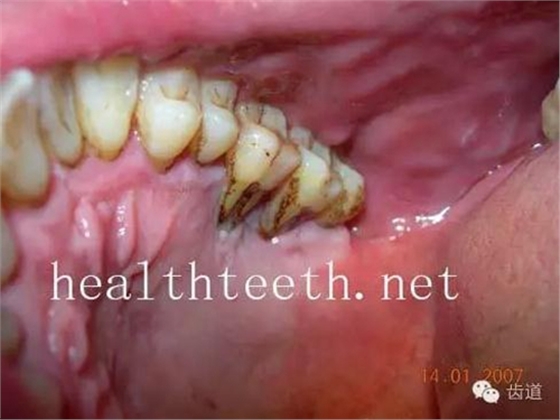

牙周大量牙石堆積

下牙的增生性齦炎,刷牙出血嚴(yán)重